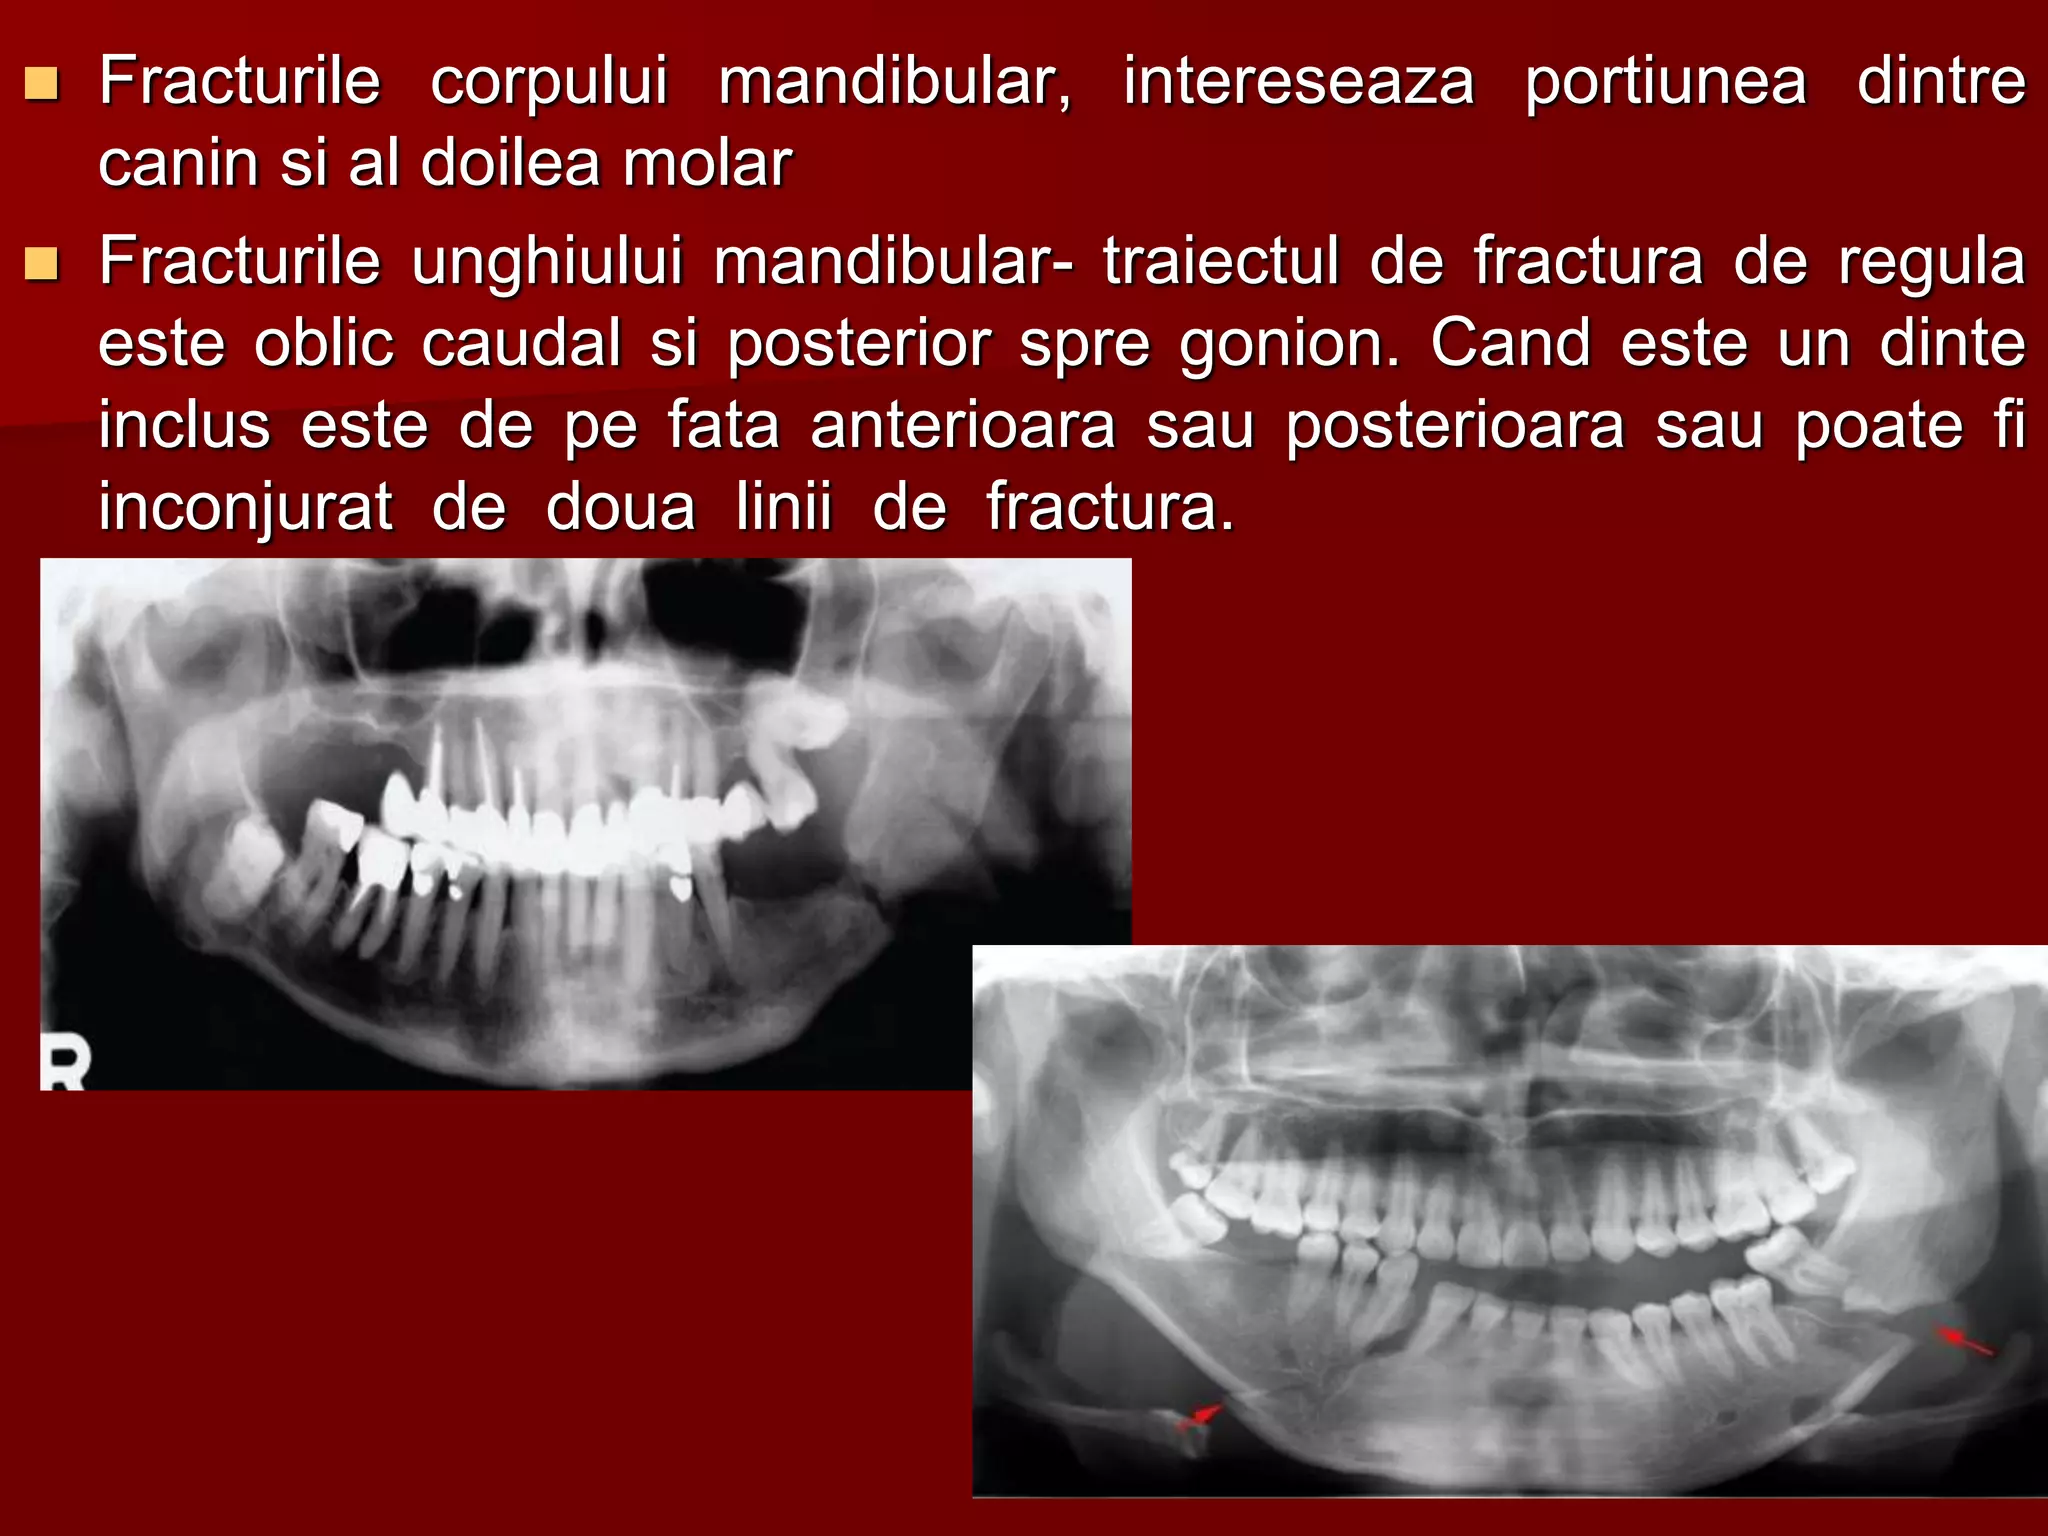

 Fracturile corpului mandibular, intereseaza portiunea dintre

canin si al doilea molar

 Fracturile unghiului mandibular- traiectul de fractura de regula

este oblic caudal si posterior spre gonion. Cand este un dinte

inclus este de pe fata anterioara sau posterioara sau poate fi

inconjurat de doua linii de fractura.